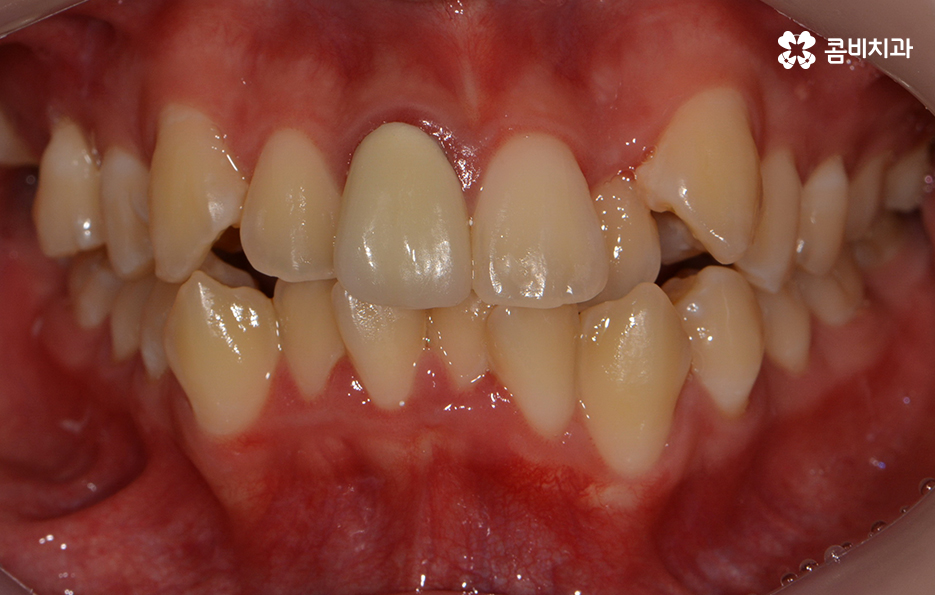

전체적으로 치열이 가지런한 편이지만 덧니가 하나 정도

눈에 띄게 있는 경우에는 귀여운 포인트로 여기는 경우도

있지만 덧니가 치아 곳곳에 심한 경우에는 웃을 때마다

콤플렉스를 느끼거나 치아 기능상의 문제, 청결 관리의

어려움 등을 느끼시는 분들도 많을 거예요.

덧니가 심한 경우에는 음식물이 치아 사이에 끼기 쉽고

심미적으로도 좋지 않기 때문에 덧니교정을 통해서

치열을 가지런하게 재배치하는 것이 필요할 수 있는데요.

왼쪽이 윗니이고 오른쪽이 아랫니인데 치열의 불규칙함이

심한 편이다 보니 평소 음식물이나 치석이 끼기 쉬운 환경이

되고 이러한 구강 환경이 지속된다면 충치와 잇몸질환의 발생률이 높아질 수 있어요.